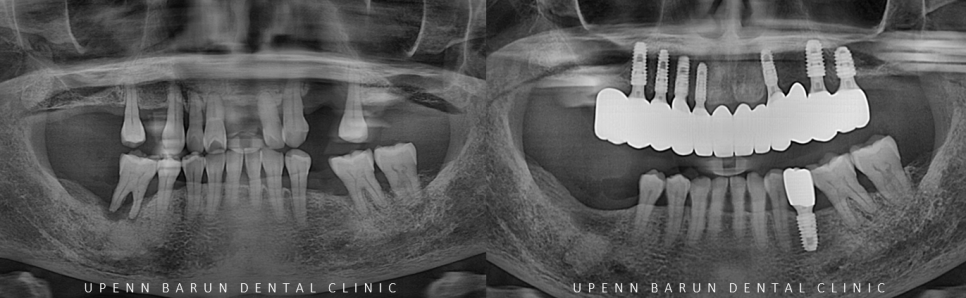

임플란트 식립 후 파노라마 엑스레이를 찍어보니

안전하고 정확하게 식립이 되었고

3개월전 식립한 임플란트도 잘 되어있었습니다.

총 치료기간 1년4개월 (22/3/28~23/7/17)

1년뒤인 23년 7월

잘 고정된 임플란트의 본을 뜨고, 최종 보철물이 완성된 사진입니다.

교합이 무너져 있었던 이전과 달리

맞물리는 치아가 생기며 환자분께서

식사를 잘 하실 수 있게 되셨어요 ㅎㅎ

(오른쪽 아래 치아의 경우 상악 임플란트가 적응되는대로 곧이어 치료를 진행하시기로 하셨습니다^^)

상악에 총 7개 임플란트를 통해

총 12개의 치아를 만들어 드렸는데요~!

임플란트를 효율적이고 정확한 위치에 심게 되면

치아의 갯수대로 전체 임플란트를 하지 않아도

임플란트끼리 연결하여 인공치아를 만들어 사용하실 수 있습니다.